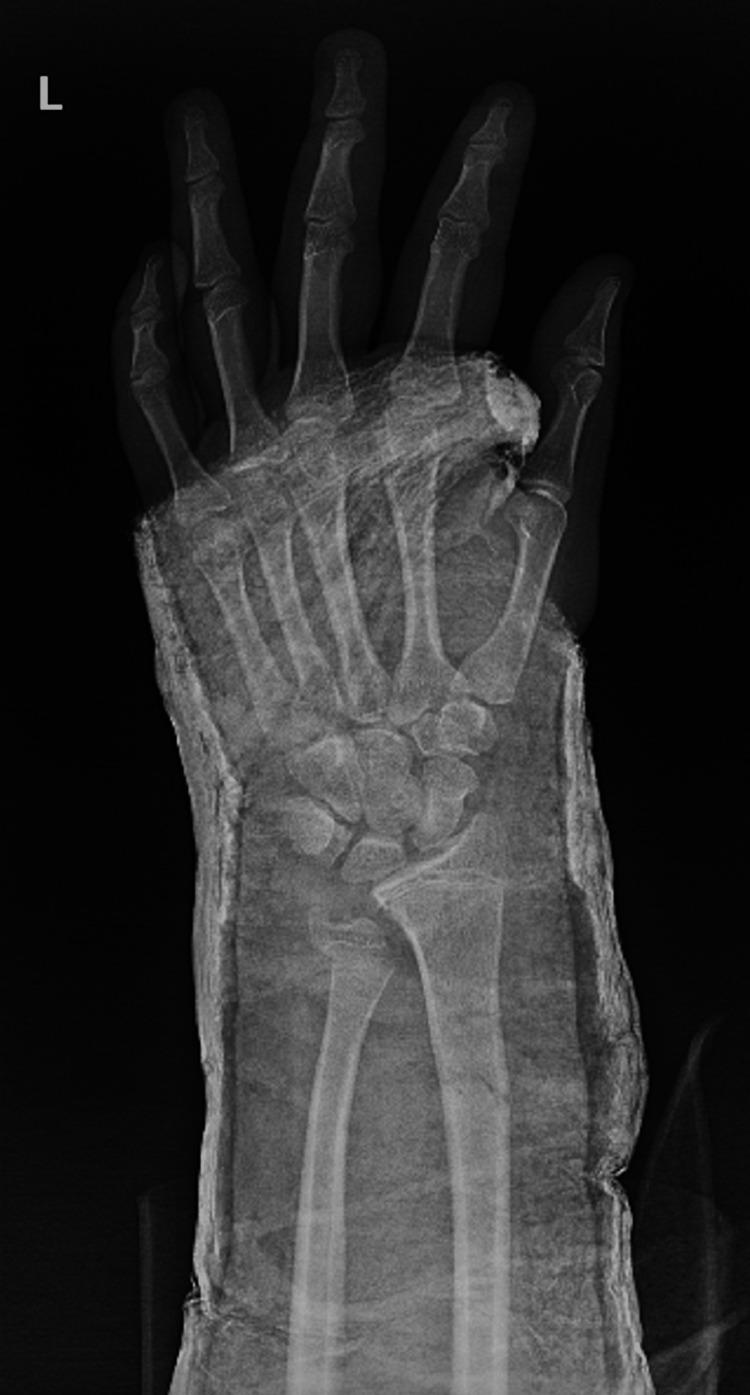

Fractures of the forearm are common among children and adolescents. Radial shaft fracture with dislocation of the distal radioulnar joint (DRUJ), called Galeazzi fracture, is unusual in pediatrics. The Galeazzi-equivalent fracture is a variant of the classic Galeazzi fracture that occurs in children and adolescents. It is a radius fracture associated with a distal ulnar displaced physeal injury without dislocation of the DRUJ. Our patient was a male, aged 15 years, who visited our emergency department after falling off a scooter onto his left hand. Left wrist X-rays showed a displaced Galeazzi-equivalent fracture. After a trial of close reduction, an X-ray showed a displaced and unstable fracture pattern. The patient was subsequently hospitalized for surgical intervention. Open reduction and internal fixation (ORIF) with a plate and screw were used for the radius fracture. The ulna fracture was irreducible; therefore, ORIF with two crossed smooth Kirschner wires (K-wires) was performed. Complete bone union was achieved, and he had a normal range of motion six months postoperatively. The patient is now able to perform daily and sports activities. At two-year follow-up, complications such as DRUJ instability or joint deformity did not occur. In conclusion, open reduction is desired for patients with malalignment or older patients who have a lower potential for sufficient bone remodeling. Regular serial follow-up sessions are required to assess growth arrest and the occurrence of other complications.

前臂骨折在儿童和青少年中很常见。桡骨干骨折合并下尺桡关节(DRUJ)脱位,即盖氏骨折,在儿科中并不常见。类盖氏骨折是经典盖氏骨折的一种变体,发生于儿童和青少年。它是一种桡骨骨折,伴有尺骨远端骨骺移位损伤,而DRUJ无脱位。我们的患者是一名15岁男性,骑滑板车时左手着地后前来我院急诊科就诊。左手腕X线片显示为移位的类盖氏骨折。试行闭合复位后,X线片显示骨折移位且不稳定。患者随后住院接受手术治疗。桡骨骨折采用钢板螺钉切开复位内固定(ORIF)。尺骨骨折无法复位;因此,采用两根交叉光滑克氏针(K针)进行ORIF。术后6个月实现了完全骨愈合,患者活动范围正常。患者现在能够进行日常和体育活动。在两年的随访中,未出现DRUJ不稳定或关节畸形等并发症。总之,对于骨折对位不良的患者或骨重塑潜力较低的年长患者,需要进行切开复位。需要定期进行系列随访,以评估生长停滞和其他并发症的发生情况。